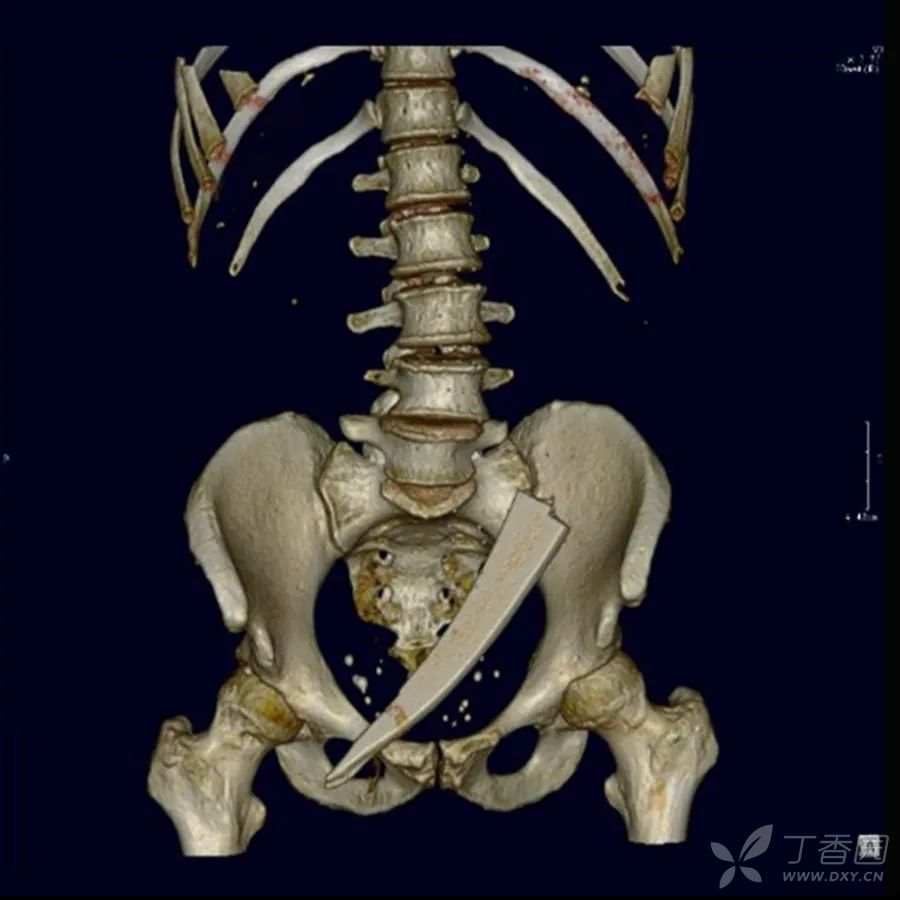

腹腔CT

在腹腔内发现一块19厘米长的玻璃碎片,在盆腔内呈环状。

剖腹手术,异物被发现并取出。没有腹部器官受伤。